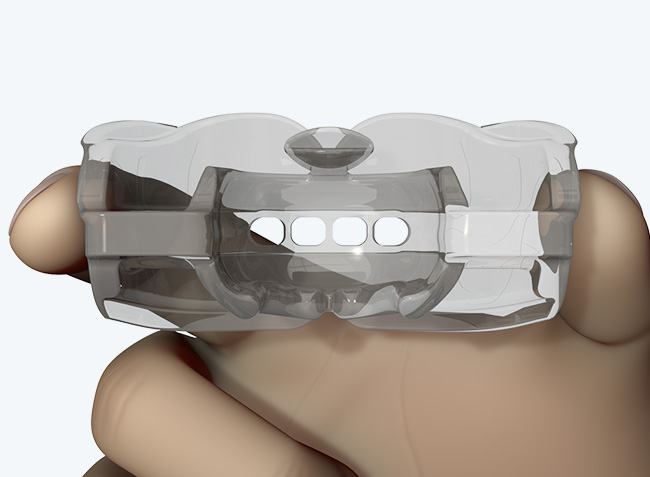

The Myosa®for TMJBDS®S1 is used in patients with a Breath Hold Time (BHT) of 20 seconds or more. It works by advancing the sleeper’s lower jaw and opening the bite, which has the effect of opening the airway. Additionally, the S1 has four breathing holes at the front to regulate breathing. For better retention during sleep, the patient can use the mouldable version of the S1 appliance (S1M). Progress to the S2 when the patient’s BHT reaches 35 seconds or more.